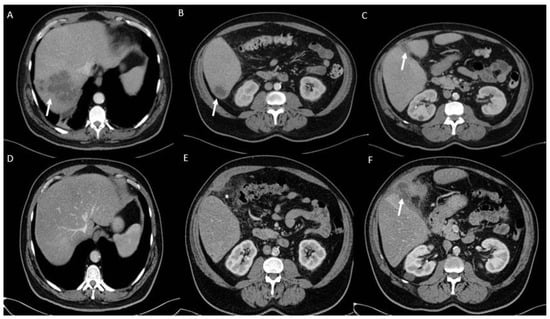

2.1. Clinical Data and Antimicrobial Susceptibility